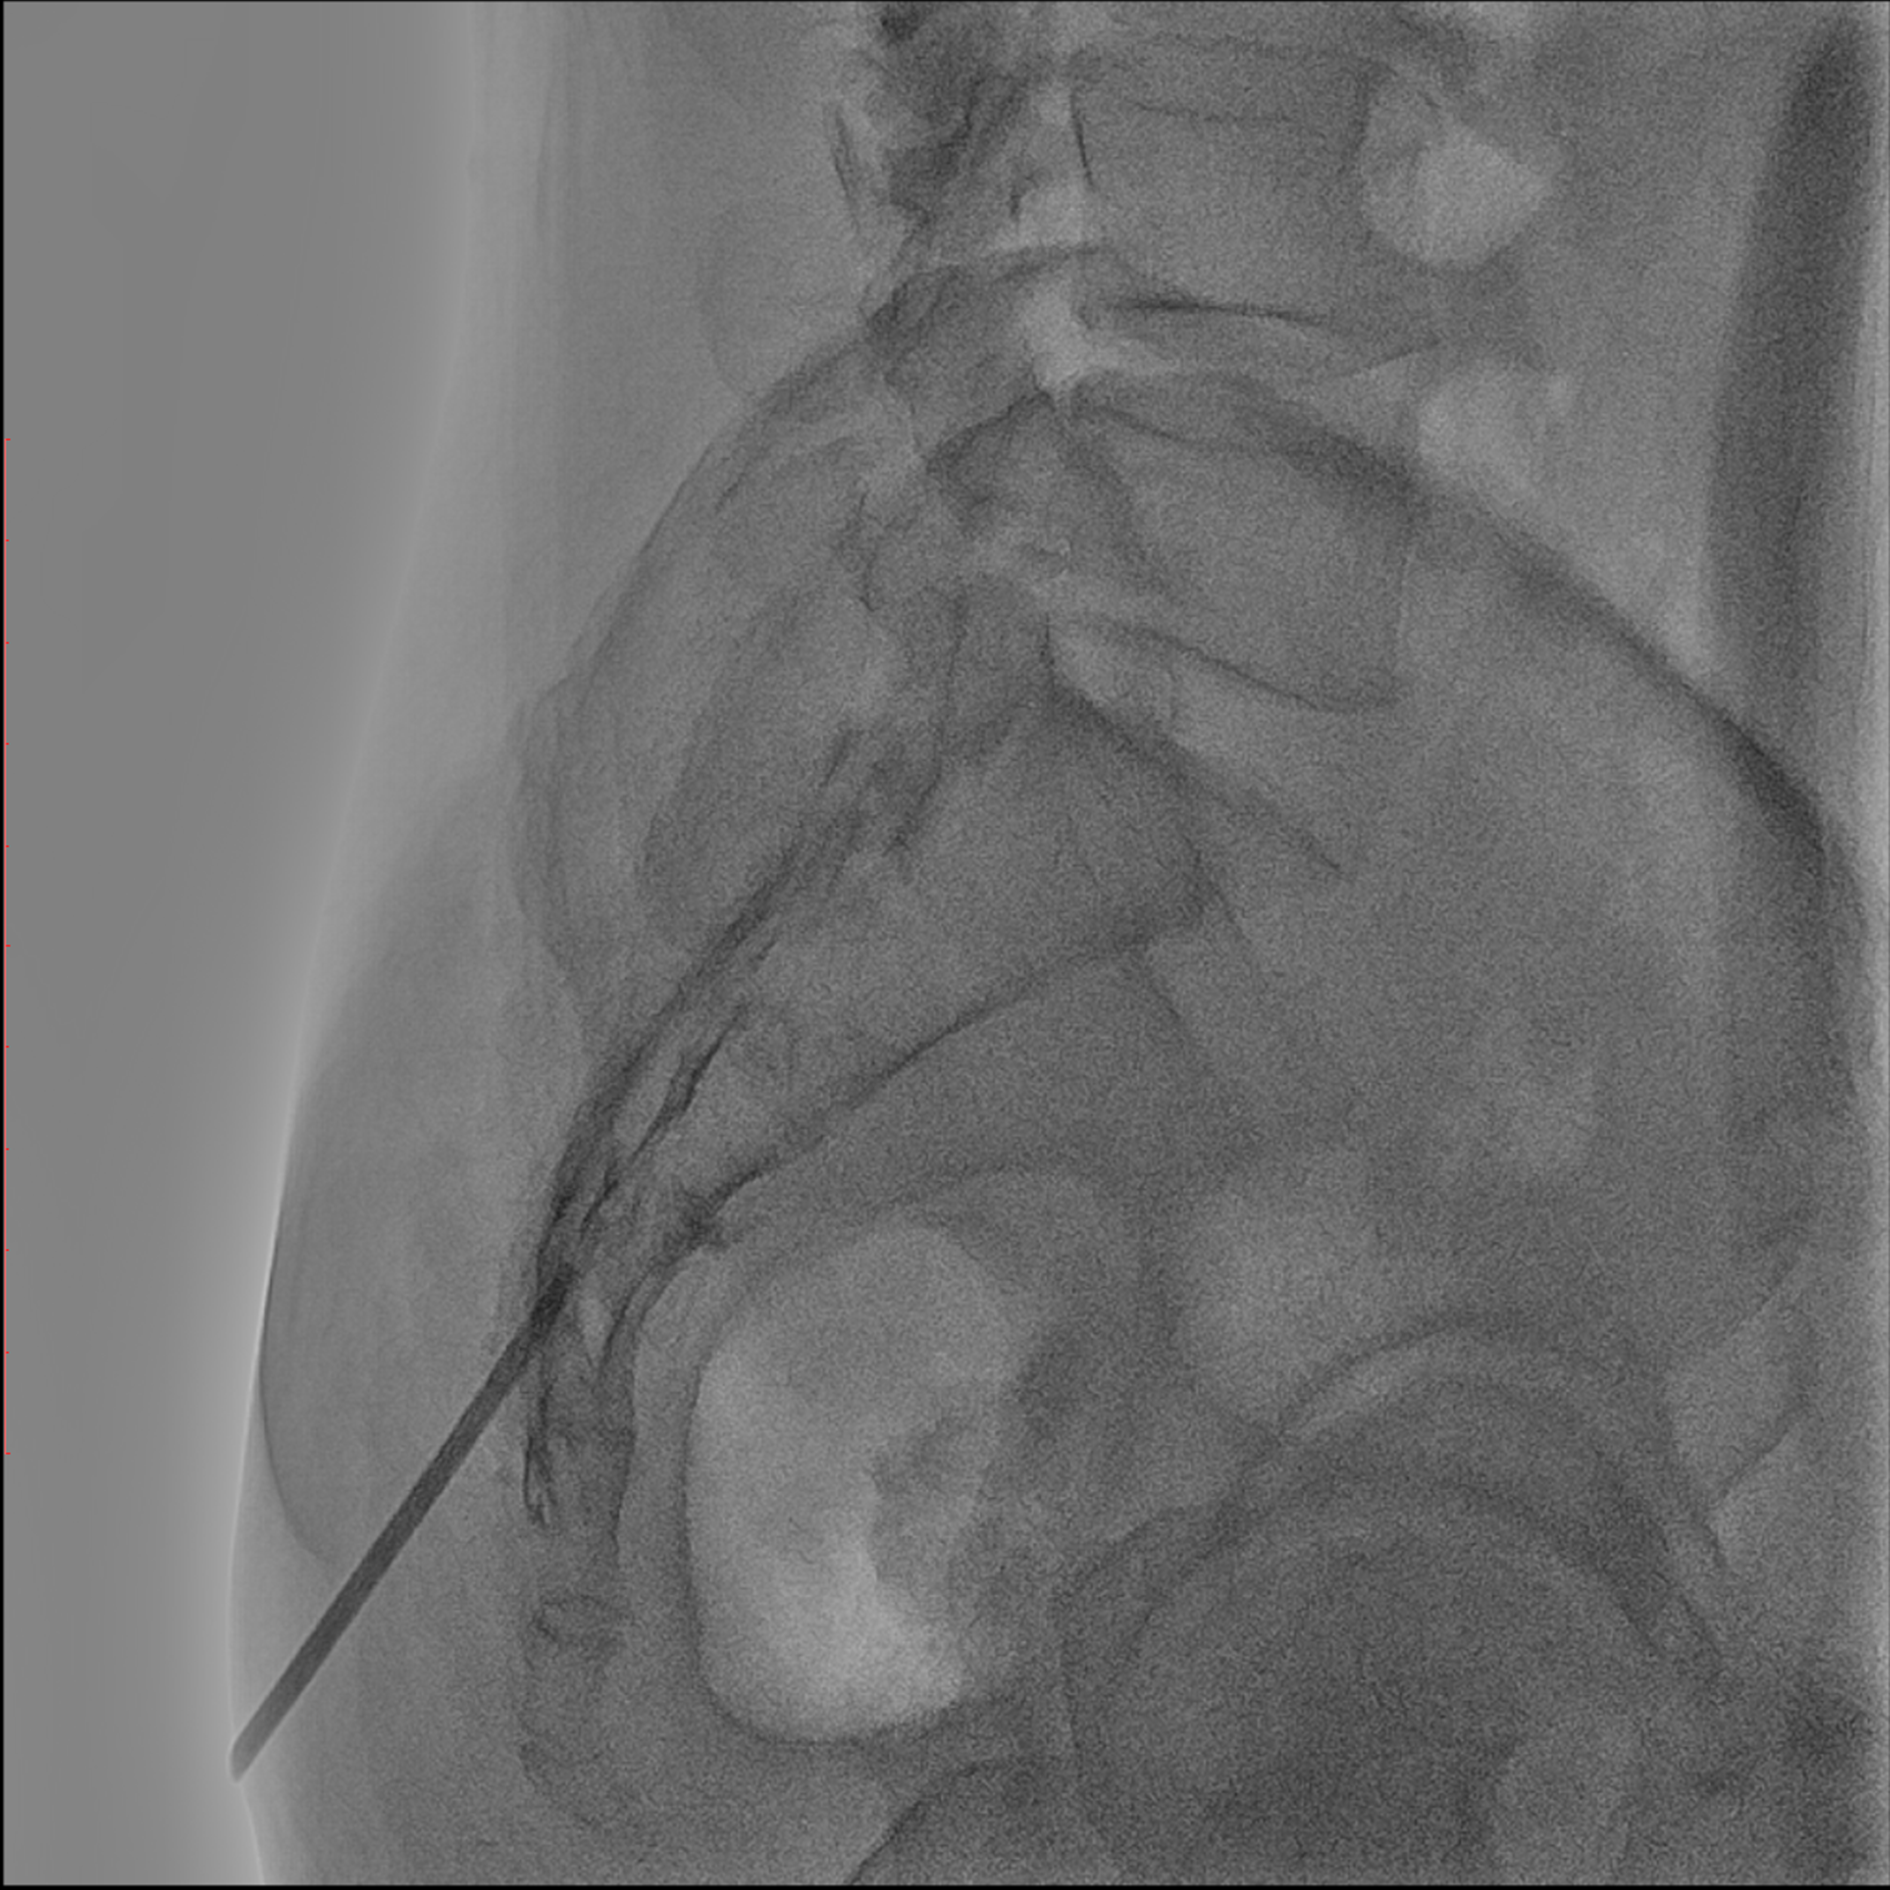

Editorial/Editor's Pick 경막외 유착박리술, Epidural Neuroplasty by Pharmacopuncture Research Lab 2026. 1. 3. 공유하기 게시글 관리 Acupuncture Radiology 관련글 MRI 요양급여의 적용기준 및 방법에 관한 세부사항 MRI 요양급여의 적용기준 및 방법에 관한 세부사항 [신구대조표] Association of AI‑determinedKellgren–Lawrence grade Portable X-ray